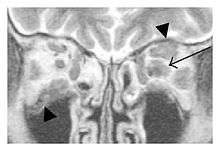

The extent of inflammation that can occur in IgG4-ROD is well demonstrated on magnetic resonance imaging (MRI).

Infraorbital nerve enlargement (IONE) is considered to be a particularly suspicious sign of IgG4-ROD, but seems to occur only when inflammation is in direct contact with the infraorbital canal.[10] IONE is defined as the infraorbital nerve diameter being greater than the optic nerve diameter in the coronal plane.

![]() Bilateral supraorbital nerve enlargements (arrows) and right infraorbital nerve (arrow head) enlargement in a 47-year-old woman with a serum IgG4 of 1000 mg/dL.[1] (T1-weighted MRI) |